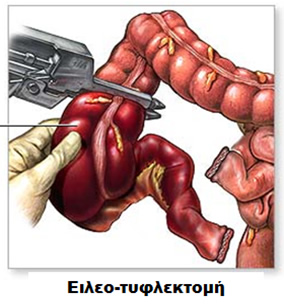

Είτε γίνει «ανοικτά» είτε λαπαροσκοπικά, η χειρουργική επέμβαση κοιλίας πραγματοποιείται για να αντιμετωπίσει το πάσχον τμήμα του εντέρου. Συνήθως, η προβληματική περιοχή εμφανίζει διάτρηση, απόφραξη ή συρίγγιο. Οι δύο πιο κοινές χειρουργικές επεμβάσεις για τη νόσο Crohn είναι η αφαίρεση του τέλους του λεπτού εντέρου και της αρχής του παχέος εντέρου, επέμβαση που ονομάζεται ειλεοτυφλεκτομή, καθώς και η αντιμετώπιση της στένωσης του εντέρου που προκαλεί την απόφραξη, με επεμβάσεις που ονομάζονται εντερεκτομές ή στενωσοπλαστικές. Σε κάθε περίπτωση σκοπός της επέμβασης είναι η διατήρηση όσο το δυνατόν μεγαλύτερου μήκους εντέρου, ώστε να παραμείνει όσο πιο φυσιολογική γίνεται η λειτουργία του πεπτικού σωλήνα που απομένει.